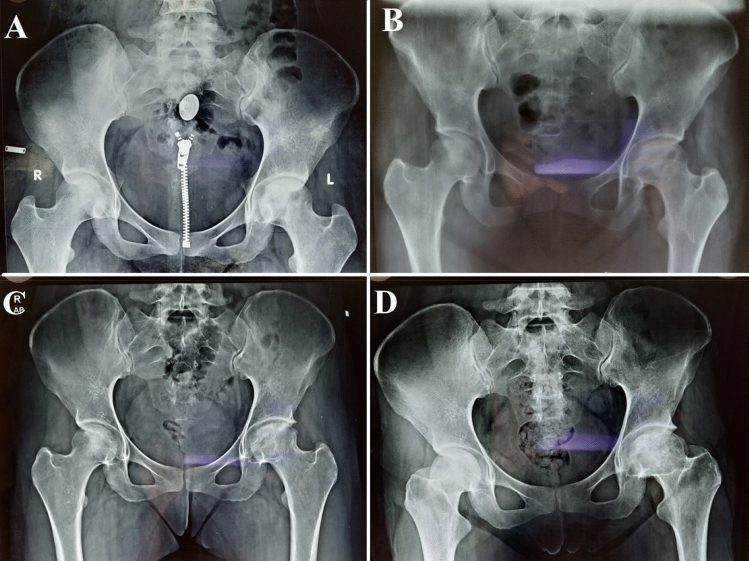

Fig. 2.

Plain radiograph of pelvis with bilateral hips (AP) showing A stage 2b left ONFH, B immediate follow-up x-ray of SVF implantation over the left femoral head, C 1-year follow-up x-ray with osteogenic activity over left femoral head, and D 4-year follow-up x-ray with maintained femoral head contour